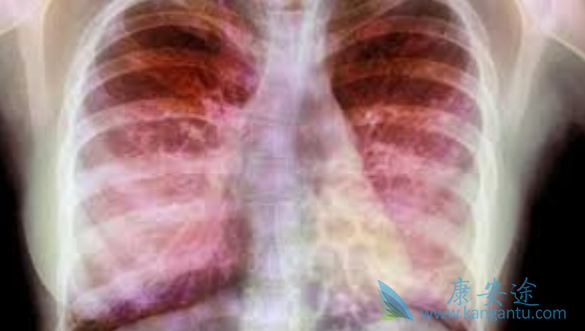

很多人常常听说肺癌、肺炎、肺结核之类的肺部疾病,却很少听说肺部纤维化,那么什么是肺部纤维化?按照专业解释来讲,肺部纤维化并不算是一种疾病,一般被称为一种病理性改变,而与肺部纤维化直接相关的疾病是“间质性肺病”。比较通俗易懂的解释来讲,肺部纤维化可以比喻为肺部发生病理性改变之后出现的“疤痕”。肺部纤维化的病人多数会因为呼吸困难、咳嗽不断、咯血而就诊,确诊之后的肺部纤维化病人可能会根据引发原因而被安排到呼吸科进行治疗。那么肺部纤维化恶毒患者该如何治疗呢?